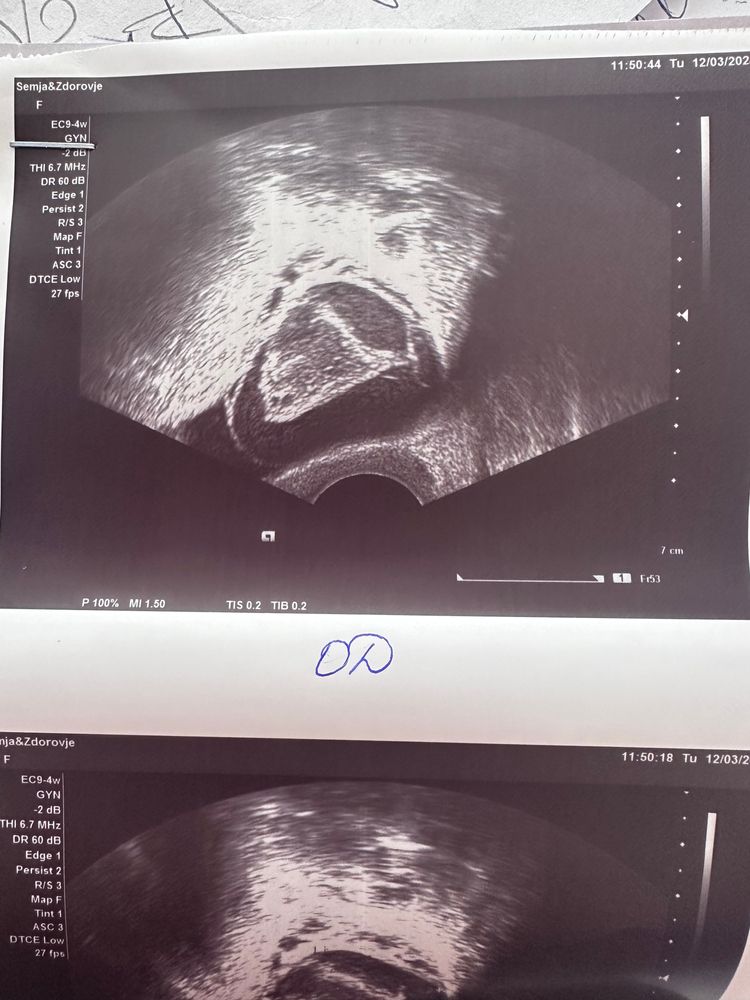

Пожалуйста 🙏🏻 помогите разобраться, какая это киста?

Неделю назад доминантный фолликул 16, эндометрий трехслойный 5.3 мм.

Тесты среда, четверг, пятница положительные на овуляцию.

Собственно поэтому я пошла сегодня на узи, чтобы не ломать себе голову. Сегодня я окончательно убедилась, что не спроста езжу к доктору за 100 км, потому что у меня в городе, не могут отличить вид кисты. На мой вопрос «какая это киста?», доктор пожала плечами. Я в шоке 😨

девочки помогите пожалуйста разобраться, я склонна к кистам желтого тела и беременность с ней была. Или это все таки мой фолликул перерос?

Алёна, почитала, сравнила в инете, что вроде как фолликулярная. Пишут что как "огненное кольцо" должно быть, если это киста желтого тела. А тут, как мне кажется, четкие контуры.

Если был дф и пик на тестах, то скорее всего жт. Узист разве не написал что за киста? Когда у меня была киста жт в заключении так и написали, что киста жт